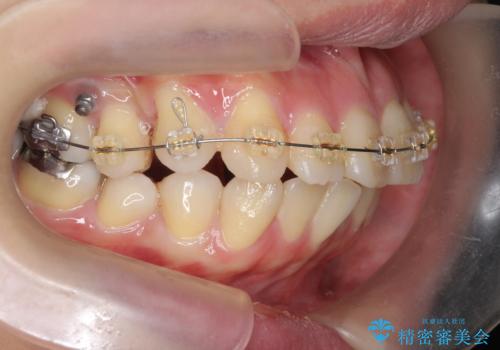

- 矯正装置

- インビザライン +部分ワイヤー矯正

マウスピースでは改善の難しい小臼歯のねじれをまず部分ワイヤー矯正で改善し、その後マウスピース矯正で前歯の突出感を改善します。

時間はかかりましたが、捻れ、かみ合わせ、前歯の角度の改善が達成され満足いただくことができました。